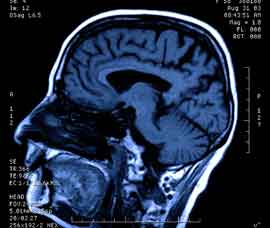

MS is a neurological condition that affects around 100,000 people in the UK. It can cause vision problems, difficulties with walking and fatigue, and tends to strike mainly young and middle-aged women.

The new research, which is published in the journal Neurology, looked at post mortem brains of MS patients, examining areas where neurological damage had recently occurred.